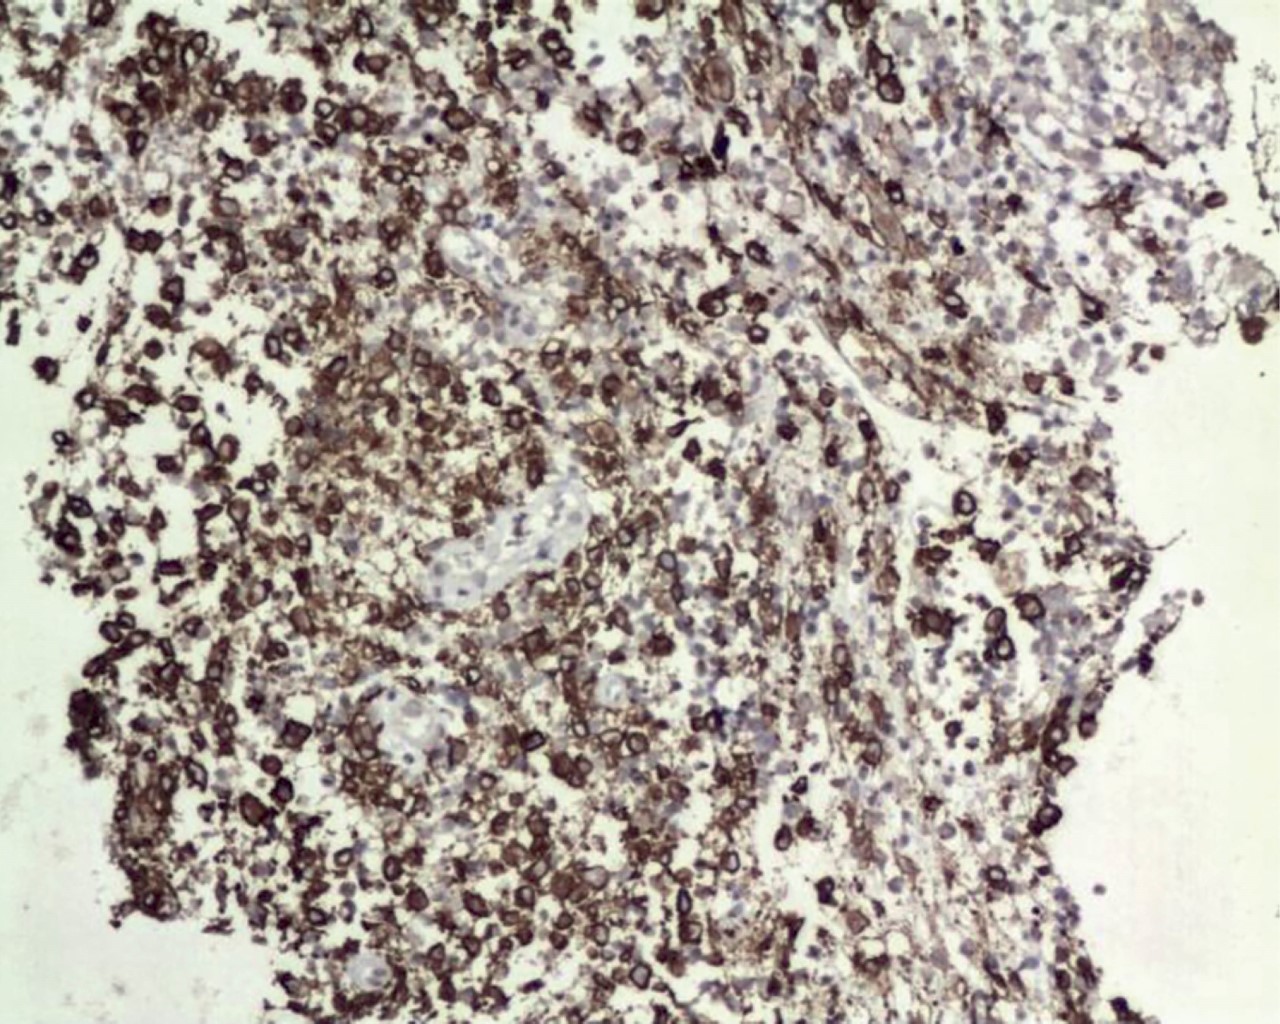

Informe histopatológico: 01/Junio/2023 el resultado indica que se identifican fragmentos de tejido fibroso laxo maduro bien vascularizado, el cual presenta áreas de hemorragia reciente y antigua, entre las que se aprecian mantos de células ovoidales y poligonales con amplio citoplasma eosinófilo, núcleos ovoidales con identaciones y pliegues centrales, entre las que se identifican numerosos eosinófilos y algunos grupos de células inflamatorias de tipo mixto.

Diagnóstico: los hallazgos son compatibles con histiocitosis de células de Langerhans.

Se confirma el estudio con el informe de inmunohistoquímica: con fecha 08/Junio/2023 en donde se obtienen resultados: S-100 positivo, CD1a positivo y Langerina positivo.

Se presenta microfotografías de cortes histopatológicos (Figuras 5, 6, 7 y 8).

Diagnóstico histopatológico. Microscopia óptica convencional: asociación de células inflamatorias con proliferación de células mononucleares grandes, redondas a ovaladas, con forma epitelioide, citoplasma eosinófilo y núcleo ranurado que recuerda a los granos de café en apariencia o riñón. Células dendríticas inmaduras sin extensiones dendríticas, que han sufrido la pérdida o una reducción significativa de algunas funciones de la célula de Langerhans normal. Producen una serie de citoquinas (interleucinas, factor de necrosis tumoral alfa [TNF-α] y factor estimulante de colonias de granulocitos y macrófagos [GM-CSF]). También se han descrito algunas mitosis y apoptosis atípicas, detectándose necrosis en casos con alta tasa de proliferación. La necrosis puede imitar otras condiciones infecciosas y neoplásicas como la tuberculosis y la enfermedad de linfoma de Hodgkin.3,18

Imnuhistoquímica. La Sociedad de Histiocitosis (Histiocyte Society) menciona que el diagnóstico histopatológico se hace según los criterios establecidos por la histología convencional y al menos dos tinciones positivas para ATP-asa, s-100, alfa-D-manosidasa o lectinas de maní.9 Cuando se utiliza microscopía de transmisión electrónica, se pueden observar los gránulos de Birbeck (estructuras en forma de varilla) ubicado en el citoplasma de las células lesionadas). El análisis inmunohistoquímico debe ser positivo para CD1a y CD207 (la langerina o CD207 es crucial para el diagnóstico ya que puede ser un indicador de la presencia de gránulos de Birbeck)16 o para anticuerpos inespecíficos como la proteína S-100.10,17,18